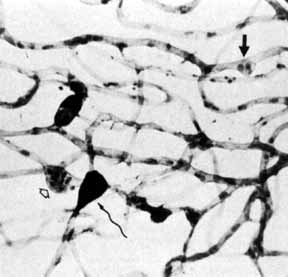

Although microaneurysms are the first ophthalmoscopically detectable change in diabetic retinopathy, the earliest abnormalities seen histopathologically are thickening of the capillary basement membrane1,2 and pericyte dropout.3,4 Pericytes are mesothelial cells that surround and support the retinal capillary endothelial cells. Normally there is one pericyte per endothelial cell. In people with diabetes, however, the pericytes die off and are decreased in number (Fig. 1). Their absence weakens the capillaries and permits thin-walled dilatations, called microaneurysms, to develop. Later, endothelial cells proliferate and lay down layers of basement membrane material. Fibrin may accumulate within the microaneurysm along with erythrocytes, and the lumen of the microaneurysm may become occluded (Fig. 2). Initially, most microaneurysms are on the venous side of the capillaries, but later they are seen on the arterial side as well. Clinically, they appear as small red dots (Fig. 3). Despite the multiple layers of basement membrane, microaneurysms are permeable to water and large molecules, allowing the transudation of fluid and lipid into the retina.

Fig. 1 A. Trypsin digest preparation of early background retinopathy. Normal retinal capillaries, with one pericyte (closed arrows) per endothelial cell (open arrows). B. Retinal capillary of a patient with diabetes with necrotic pericytes (arrows). (Courtesy of Dr. Myron Yanoff)